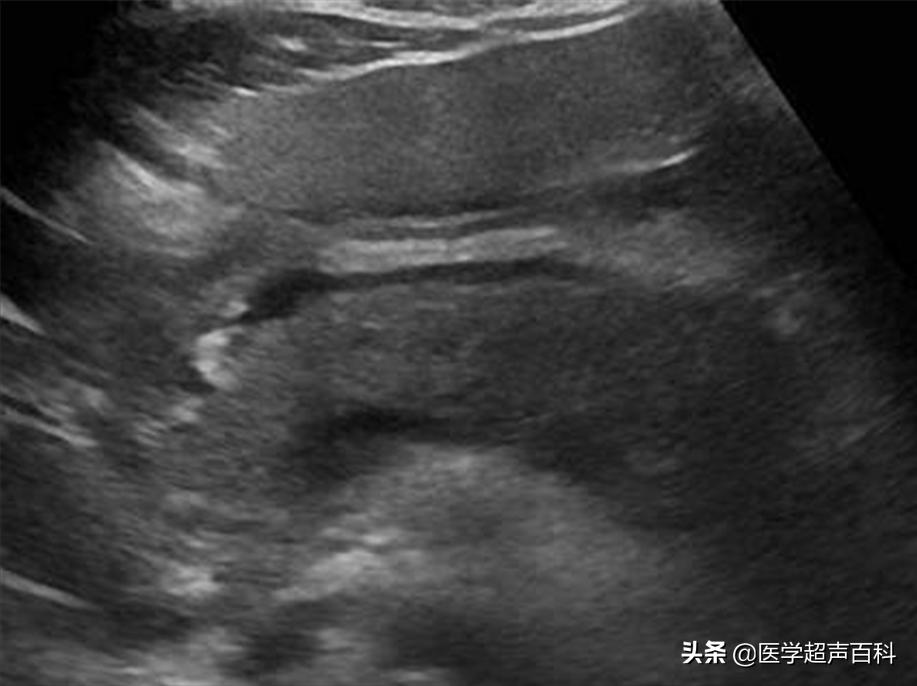

水肿型胰腺炎:胰腺弥漫性增大,边缘形态规整,内部回声减低,胰腺后方血管受压迫显示不清